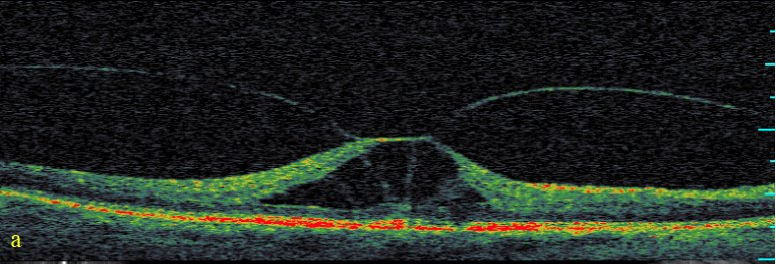

Scenario image